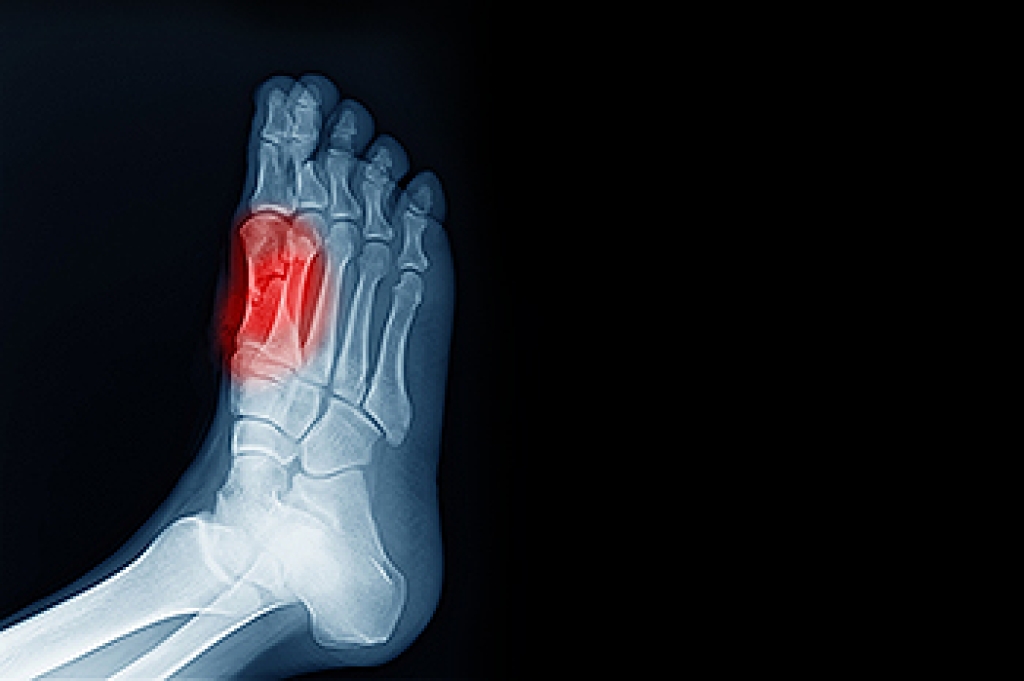

Sesamoiditis is a condition of the foot that affects the ball of the foot. It is more common in younger people than it is in older people. It can also occur with people who have begun a new exercise program, since their bodies are adjusting to the new physical regimen. Pain may also be caused by the inflammation of tendons surrounding the bones. It is important to seek treatment in its early stages because if you ignore the pain, this condition can lead to more serious problems such as severe irritation and bone fractures.

Treatment for sesamoiditis is non-invasive and simple. Doctors may recommend a strict rest period where the patient forgoes most physical activity. This will help give the patient time to heal their feet through limited activity. For serious cases, it is best to speak with your doctor to determine a treatment option that will help your specific needs.